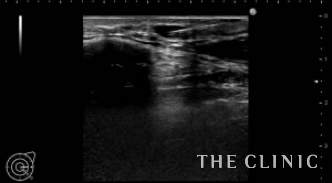

ヒアルロン酸注入によるしこりのエコー診断カルテ